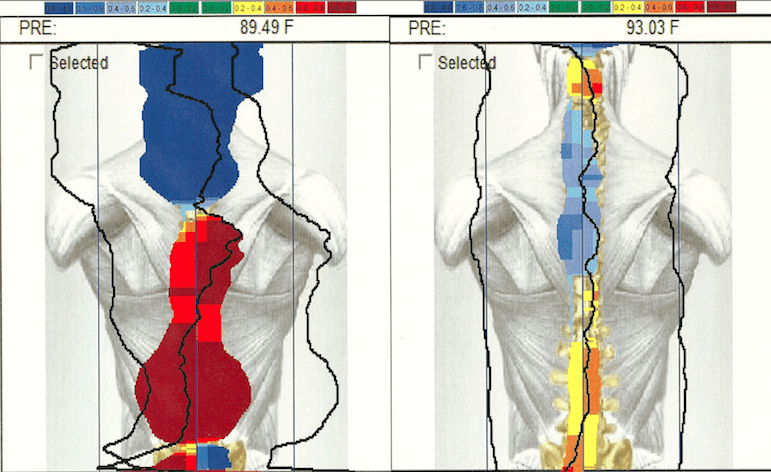

- Full spine infrared thermography exam